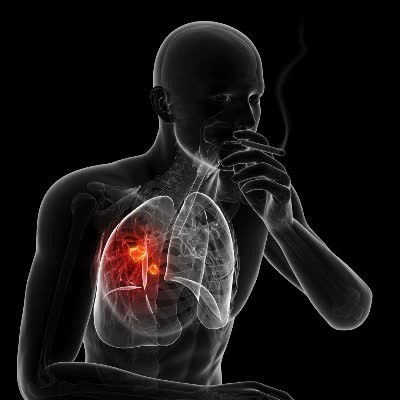

오늘은 많은 분들이 궁금해하는 폐암 초기 증상에 대해 이야기하려 합니다. 폐암은 한국인의 사망 원인 1위인 암으로, 초기에는 뚜렷한 증상이 없거나 감기와 비슷해 간과하기 쉽습니다.

- 금연: 흡연은 폐암의 가장 큰 원인이므로, 반드시 금연해야 합니다.